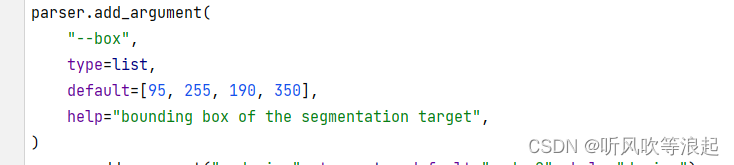

参数如下:

-i input_img

-o output path

--box bounding box of the segmentation target

因为SAM模型需要提示工程,所以传参的时候,也需要指定。这里是边界框,默认给定了。如果想要检测其他区域,需要更改这个bbox到自己想要推理的区域